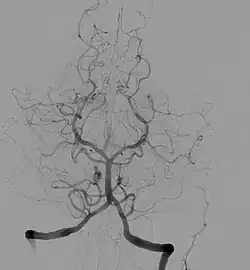

Angiographic image of normal cerebral anatomy. This illustration serves to show the reader the general circular shape of the roadmap of arteries that supply the brain. This is an x-ray image of the head after a radio-opaque dye was injected into the arterial system, the image is called an angiogram. For more detailed discussion of anatomy, see Circle of Willis.